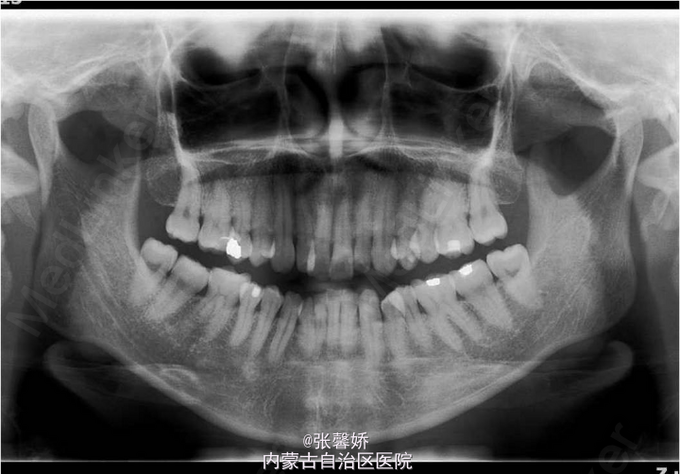

上中线右偏1mm,A2、D4反合,A2、B2畸形牙偏小,拥挤度上颌4mm、下颌6mm。Spee曲线:左侧3mm,右侧2.5mm

牙列中度拥挤;A2、D4反合 处理:时代天使隐形矫治器矫治 拔除C8、D8 适当下前牙邻面去釉 排齐整平上下牙列,改正A2、D4反合 治疗时间2年左右,矫治后牙齿排列整齐,咬合关系良好,患者满意。

一年后随访,患者咬合关系仍稳定,尖窝锁结良好。 隐形矫治适应证的选择很重要,适合中低难度的成人病例,患者的配合和依从性要求较高。 此患者术前全景片可见多个充填物,为龋易感患者,而且牙周也不是很好,隐形矫治没有拖槽更利于患者口腔卫生的维护,防止龋病的发生和牙周病的加重。